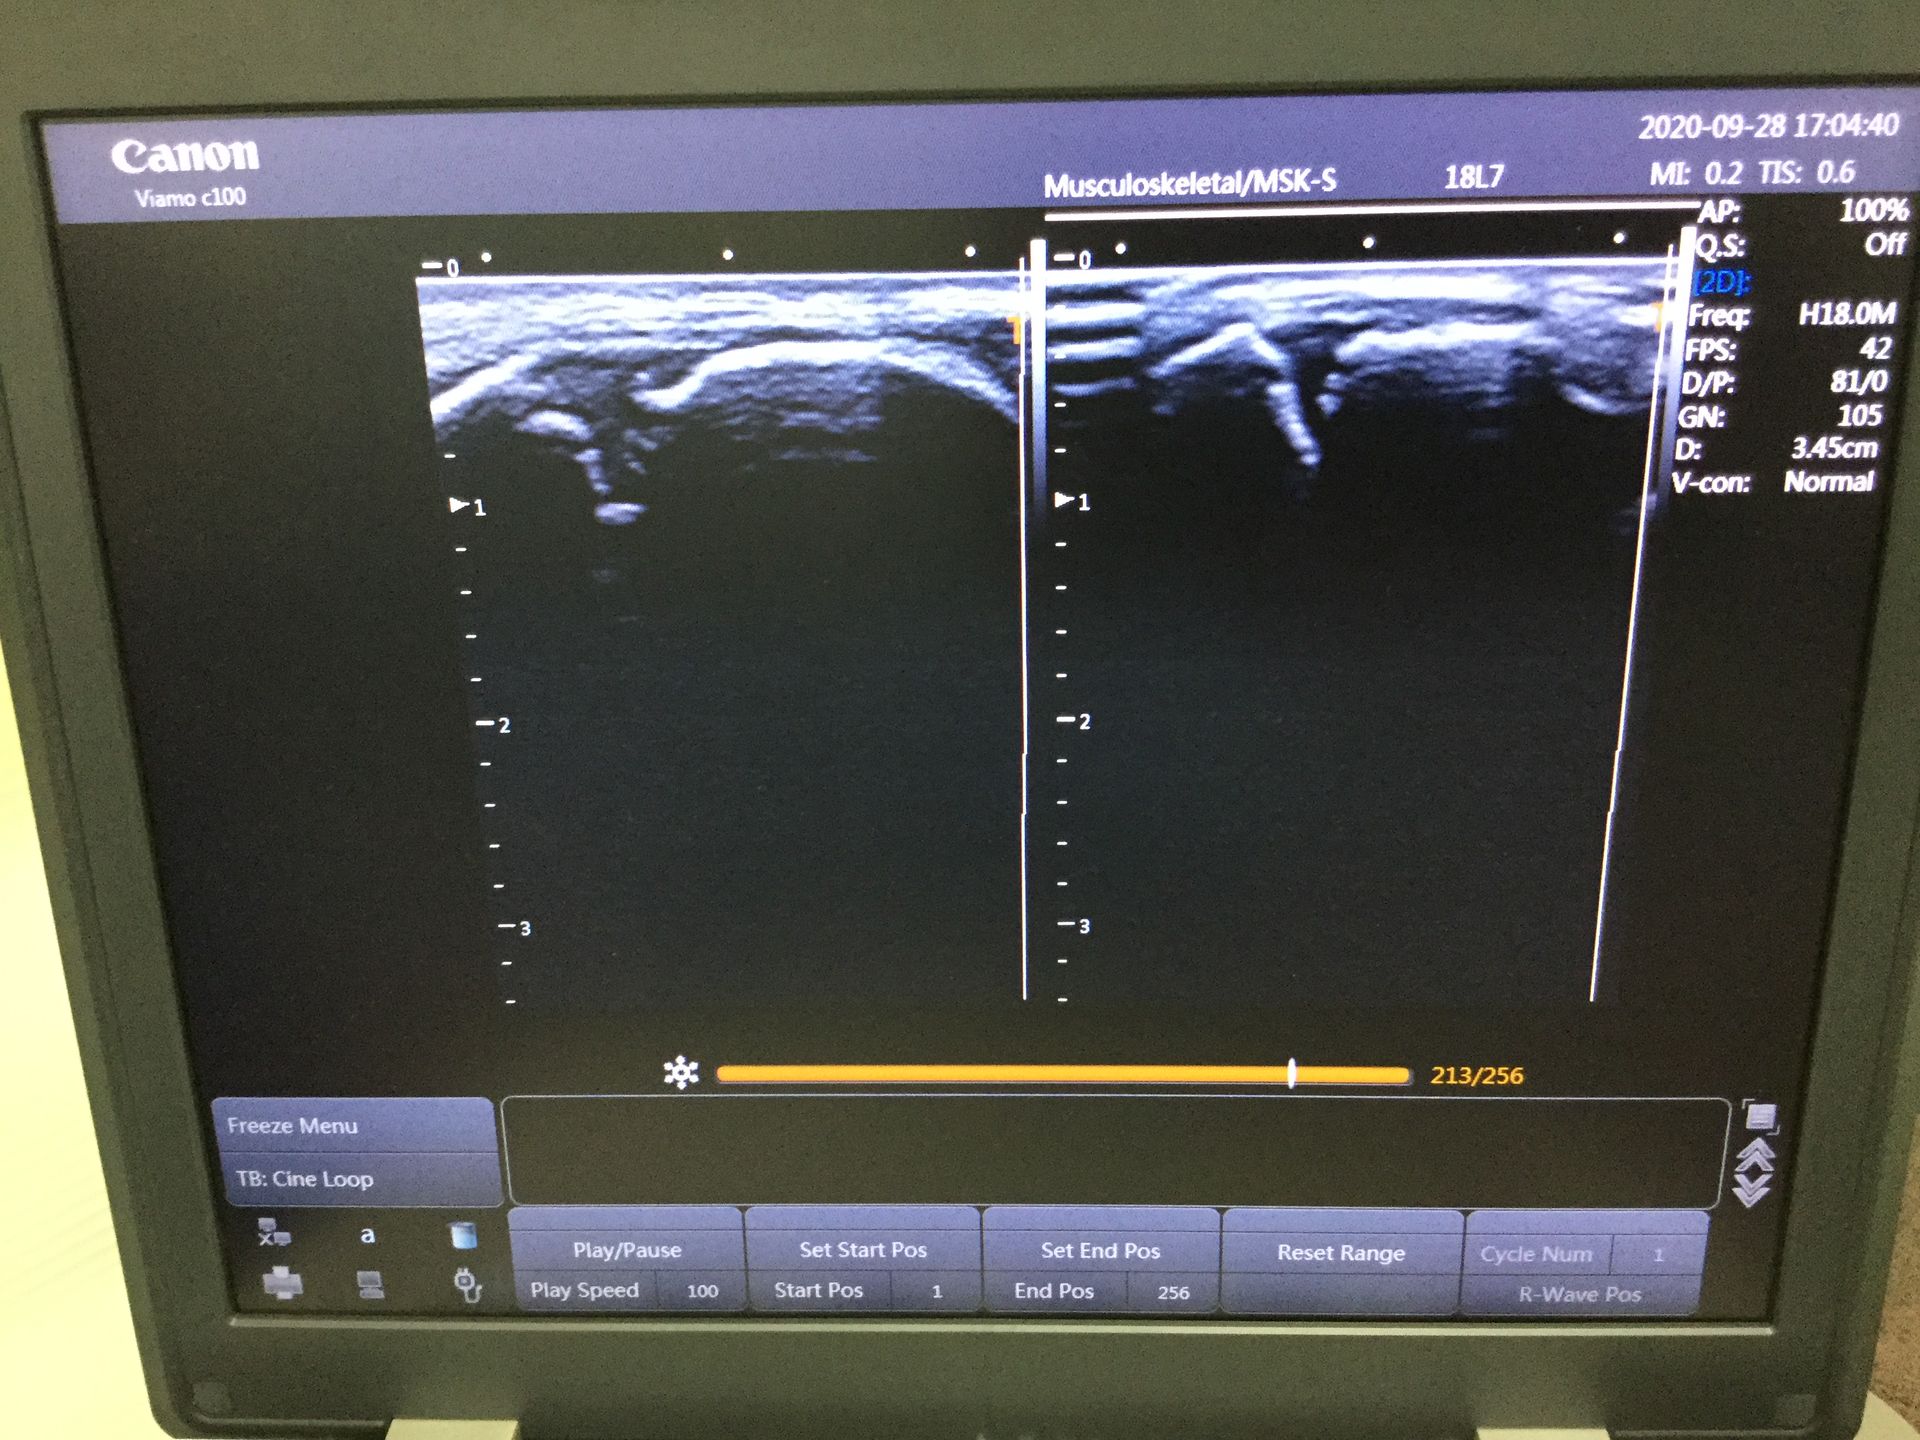

エコーで確認したところ骨端線の離開が見られました。

男の子の場合、骨が縦の成長していくための成長軟骨が高校生くらいまで存在します。この患者様はその成長軟骨と骨が付着している部分を捻っていました。

下にこの患者様のエコー像を添付しているのでご覧ください。痛めている足と反対の足を並べています。左側が痛めている足になります。

骨端線離開の場合、レントゲンなどでは見えづらい事もあり軽度の捻挫と診断されてしまう場合があります。

この患者様も当院に来院される前に病院で診察してもらったそうですが、レントゲンでは確認できなかったそうです。